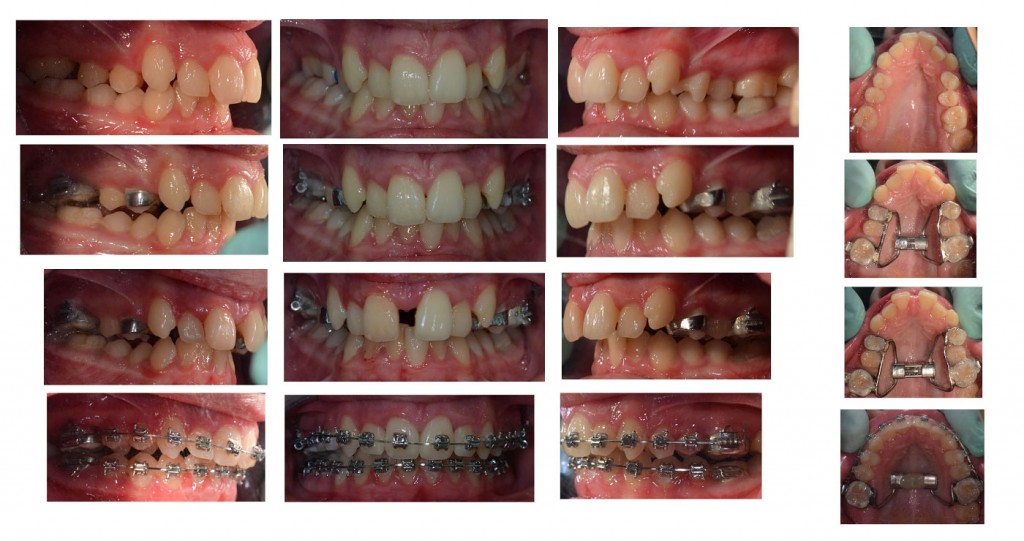

U sljedećim galerijama možete vidjeti primjere upotrebe Hyraxa:

4. primjer – jednostrani rascjep nepca

6. primjer – pseudoprogenija i hypodontia (nedostatak) gornjih trajnih lateralnih sjekutića. Osim hyraxa, pacijent nosi i Delairovu masku za stimulaciju rasta gornje čeljusti.

Slike završetka terapije

Na superpoziciji lateralne slike glave prije i poslije terapije se vide promjene u rastu.

Stanje prije terapije je označeno crvenom bojom, a zelenom je označeno stanje poslije terapije